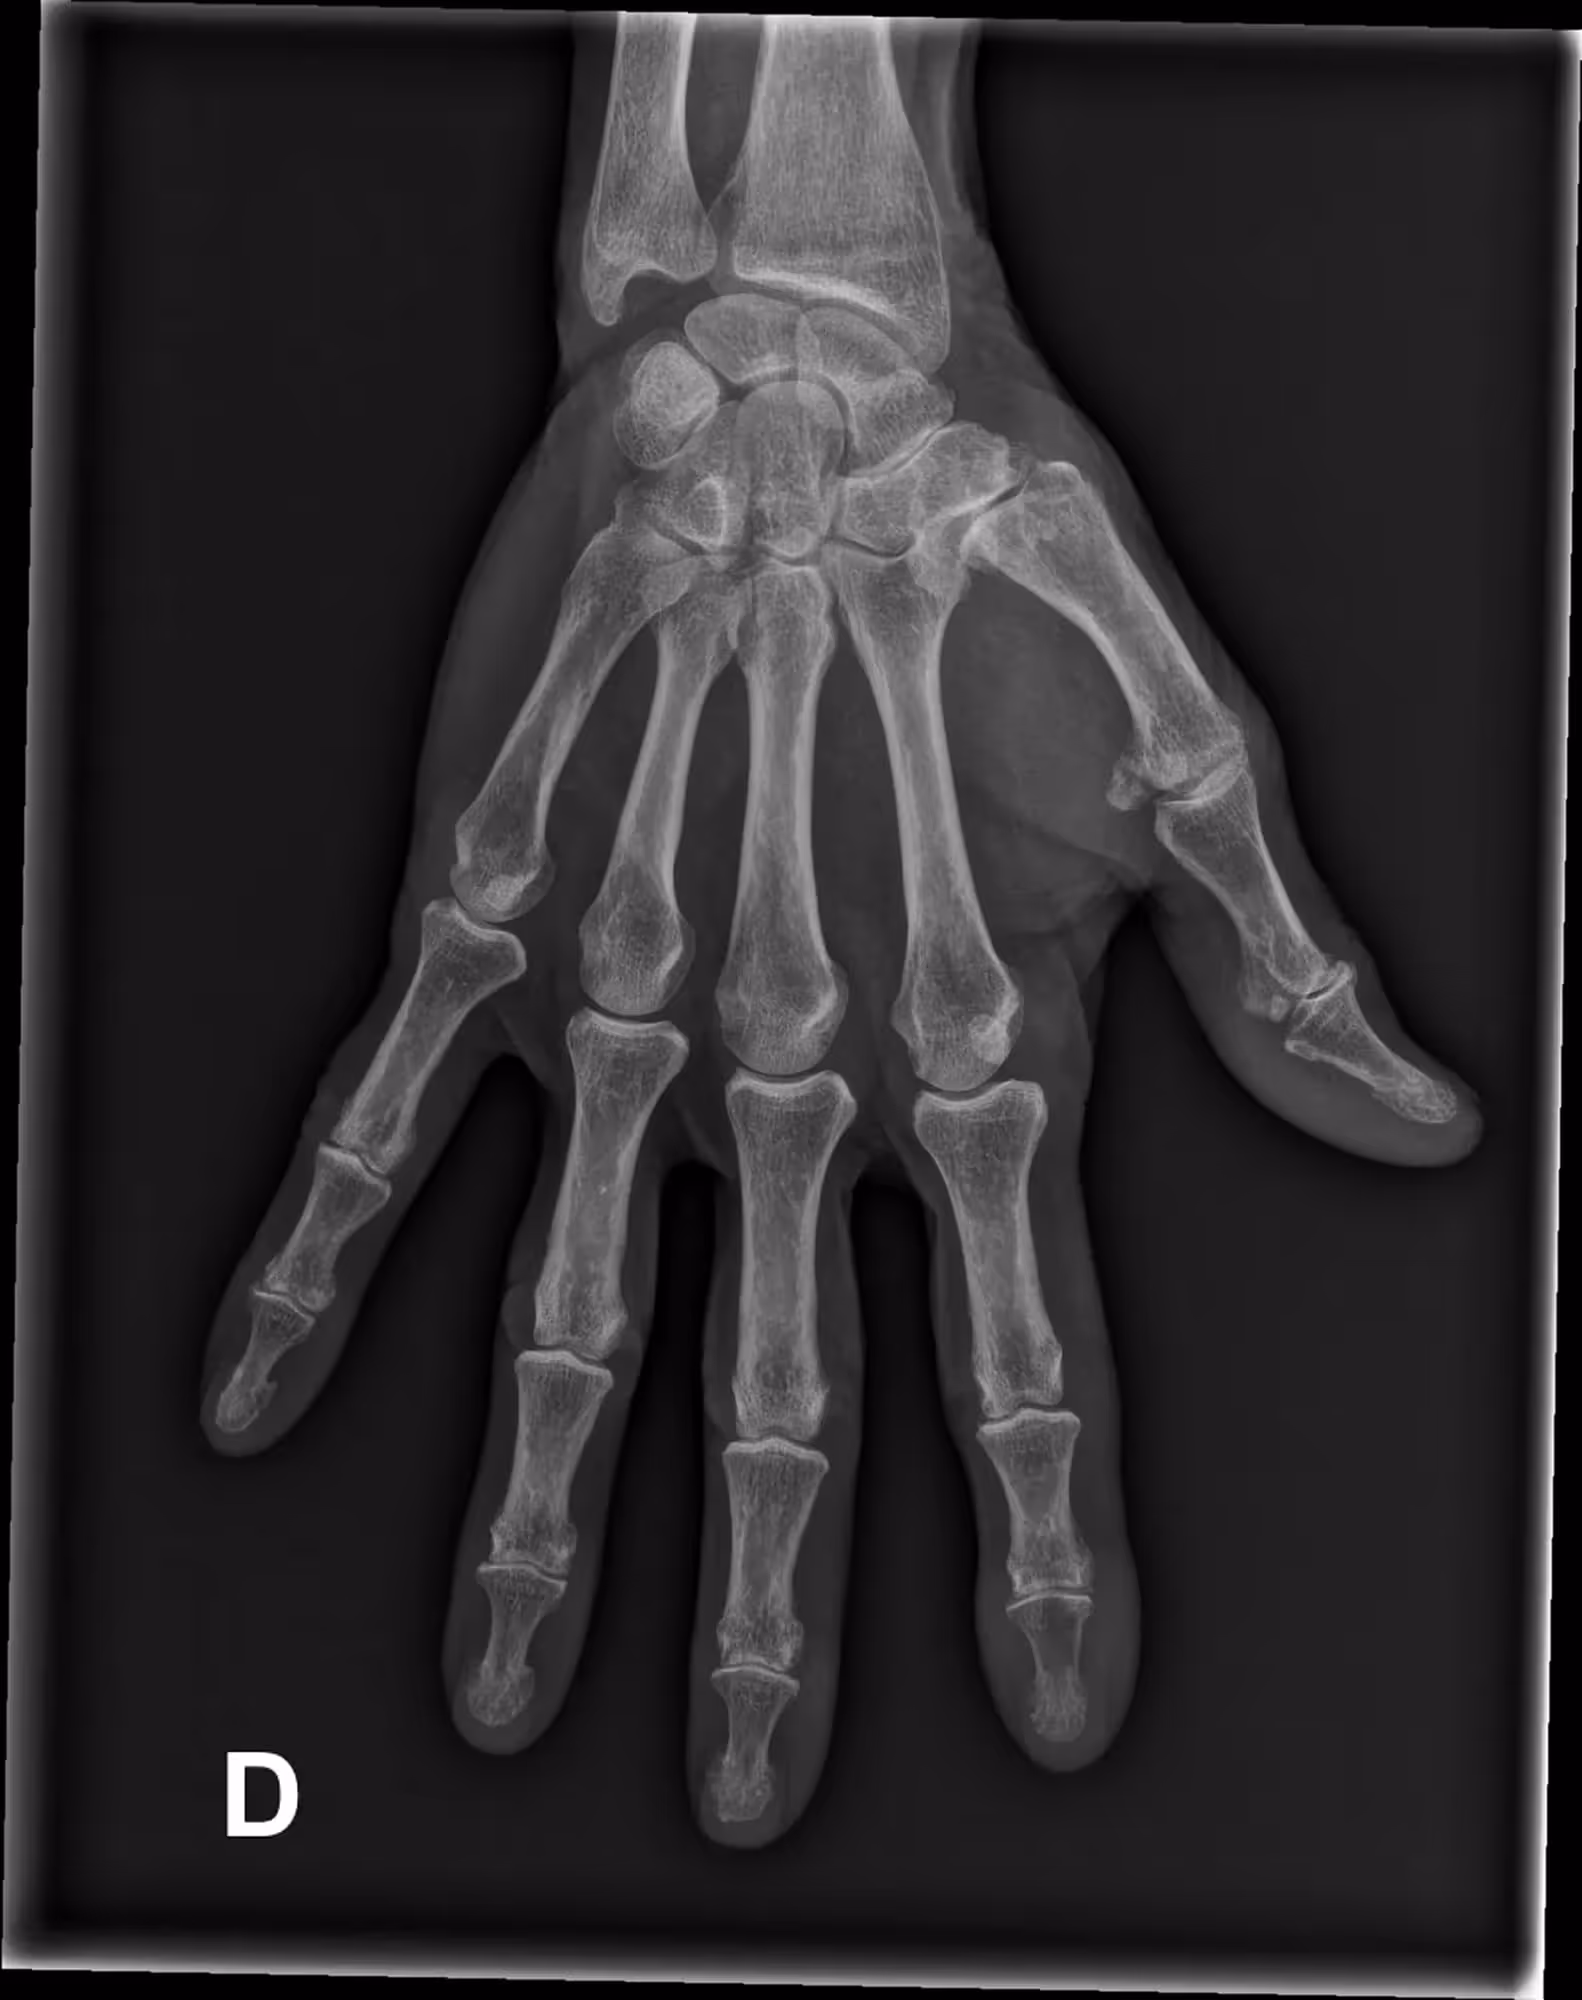

A 63-year-old male with lingering pain after a trail run.

Results

BoneView detected a fracture of the lateral tibial plateau and associated effusion. The fracture has a high risk of displacement.